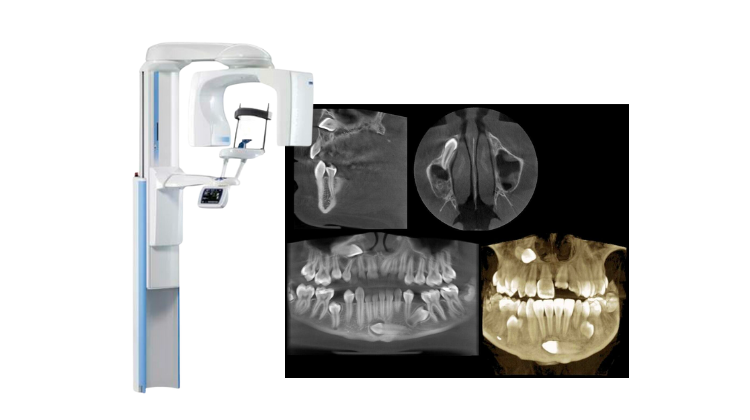

Before addressing CBCT, we must correct a critical misconception: Structured Light and Laser Triangulation are intraoral scanning (IOS) technologies, not CBCT methodologies. Conflating these indicates fundamental confusion in the market. CBCT (Cone Beam Computed Tomography) relies on X-ray projection physics and tomographic reconstruction. This review focuses exclusively on CBCT advancements relevant to dental implant planning, endodontic diagnostics, and surgical guidance.

Core Technology Advancements in 2026 CBCT Systems

The “best” dental CBCT in 2026 is defined by three interdependent engineering pillars: detector quantum efficiency, iterative reconstruction fidelity, and AI-driven workflow integration. Marketing terms like “high resolution” are meaningless without specifying dose context and reconstruction parameters.

1. Detector Technology: Beyond Pixel Count